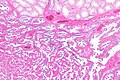

Adenomatous hyperplasia of the rete testis

Adenomatous hyperplasia of the rete testis. H&E stain. | |

| LM | epithelium with tubulopapillary or cribriform architecture separated by small amount of stroma |

Adenomatous hyperplasia of the rete testis (abbreviated AHRT), also rete testis adenomatous hyperplasia, is a rare benign lesion of the rete testis that may be confused with malignancy.[1][2]

- Epithelium with tubulopapillary or cribriform architecture separated by small amount of stroma.